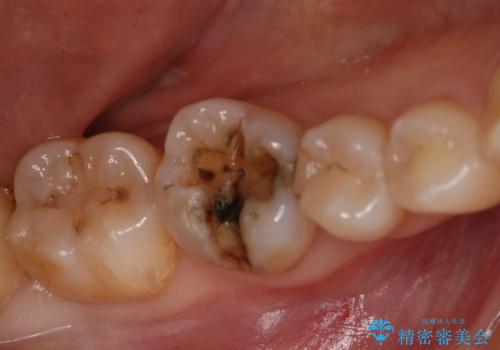

- 右下6番のメタルインレー脱離のため来院。

セラミックの治療を希望されたため切削量を考慮し、セラミックインレーでの治療を選択しました。

う蝕が深くまで進行していたので、CRで裏層した上で形成・印象をしています。